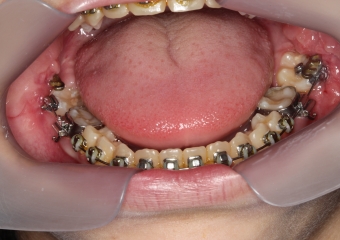

Dentes em tracionamento, imediatamente após a cirurgia - Clínica Cliniface

Dentes em tracionamento, imediatamente após a cirurgia